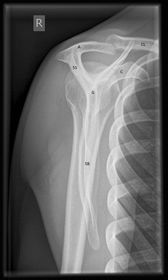

| AP Clavicle | ANATOMY: entire clavicle with both AC and SC joints included CRITERIA: entire clavicle and acromion are included lateral clavicle bows up, while the medial clavicle is superimposed by ribs 2-3 POSITIONING: CR perpendicular @ midclavicle |

| AP Axial Clavicle | ANATOMY: entire clavicle and both joints included CRITERIA: clavicle is more horizontal, and projected above the scapula and ribs medial end may be superimposed by ribs POSITIONING: CR angled 15-30 degrees cephalic @ midclavicle |

| AC Joints | ANATOMY: Bilateral AC joints included and open CRITERIA: non weight bearing and weight bearing projections marked correctly both joints included lateral clavicle almost horizontal POSITIONING: CR perpendicular @ jugular notch |